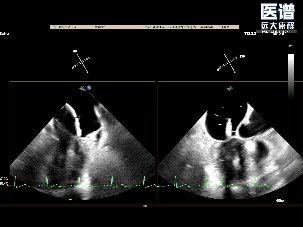

术后平均压差为3mmHg

术中完成房间隔穿刺后,将可操控导引导管(SGC)及二尖瓣夹输送系统成功送入左心房。随后将瓣膜夹调整至二尖瓣上并逐步移至病变区域,经轴向调整后,夹合器于A1/P1交界区顺利捕获瓣叶并完成首次夹合,此时超声提示存在少量反流;为达到更优的治疗效果,王建安院士及刘先宝教授决定微调位置,打开夹合器调整轴向后,重新捕获瓣叶以夹合瓣叶并成功释放,最终有效解决了反流及脱垂问题。释放后食道超声评估仅存在少量反流,平均跨瓣压3mmHg,圆满完成手术。